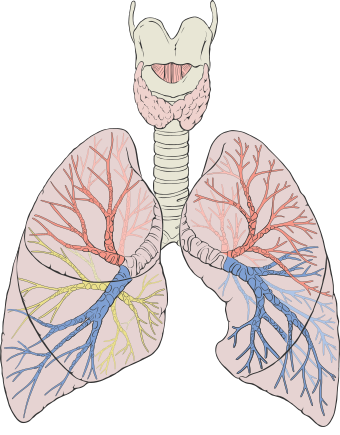

![]() رسم تخطيطي لرئتين بشريتين حيث يظهر الجهاز التنفسي، وألوان مختلفة لكل فص. | |

للبشر رئتان، رئة يمنى ورئة يسرى. وتقعان داخل تجويف الصدر. الرئة اليمنى أكبر من اليسرى، والرئة اليسرى تتقاسم مساحة الصدر مع القلب. ويبلغ وزن الرئتين معًا حوالي 1.3 كيلوجرام، والرئة اليمنى أثقل. الرئتان هما جزء من السبيل التنفسي السفلي الذي يبدأ عند القصبة الهوائية ويتفرع إلى الشعب والشعبيات الهوائية، والتي تتلقى الهواء الذي يتم استنشاقه عبر المنطقة الموصلة. تنقسم هذه حتى يصل الهواء إلى الحويصلات الهوائية المجهرية، حيث يحدث تبادل الغازات. تحتوي الرئتان معاً على ما يقرب من 2.400 كيلومتر من مجاري الهواء و300-500 مليون حويصلة هوائية. كل رئة محاطة بكيس جنبي بزوج من الأغشية الجنبية مما يسمح للجدران الداخلية والخارجية بالانزلاق فوق بعضها البعض أثناء التنفس، دون الكثير من الاحتكاك. تقسم الجنبة الحشوية الداخلية كل رئة إلى شقوق في الرئة ومن ثم أقسام تسمى الفصوص. تحتوي الرئة اليمنى على ثلاثة فصوص والرئة اليسرى على فصين. تنقسم الفصوص إلى قطع قصبية رئوية وفصيصات. تتمتع الرئتان بإمداد دموي فريد، حيث تتلقى الدم غير المؤكسج المرسل من القلب لغرض تلقي الأكسجين (الدورة الدموية الرئوية) وإمداد منفصل من الدم المؤكسج (الدورة الدموية القصبية).

لدى البشر، تقع الرئتان في الصدر على جانبي القلب في القفص الصدري. وهي مخروطية الشكل ذات قمة مستديرة ضيقة في الأعلى، وقاعدة مقعرة عريضة ترتكز على السطح المحدب للحجاب الحاجز.[1] تمتد قمة الرئة إلى جذر العنق، وتصل إلى ما فوق مستوى نهاية القص من الضلع الأول. تمتد الرئتان من قرب فقرات القفص الصدري إلى مقدمة الصدر وإلى الأسفل من الجزء السفلي من القصبة الهوائية إلى الحجاب الحاجز.[1]

تنقسم كل رئة إلى أقسام تسمى الفصوص بواسطة طيات الغشاء الجنبي الحشوية على شكل شقوق. تنقسم الفصوص إلى قطع، ولكل قطعة أقسام أخرى تسمى الفصيصات. يوجد ثلاثة فصوص في الرئة اليمنى وفصان في الرئة اليسرى.